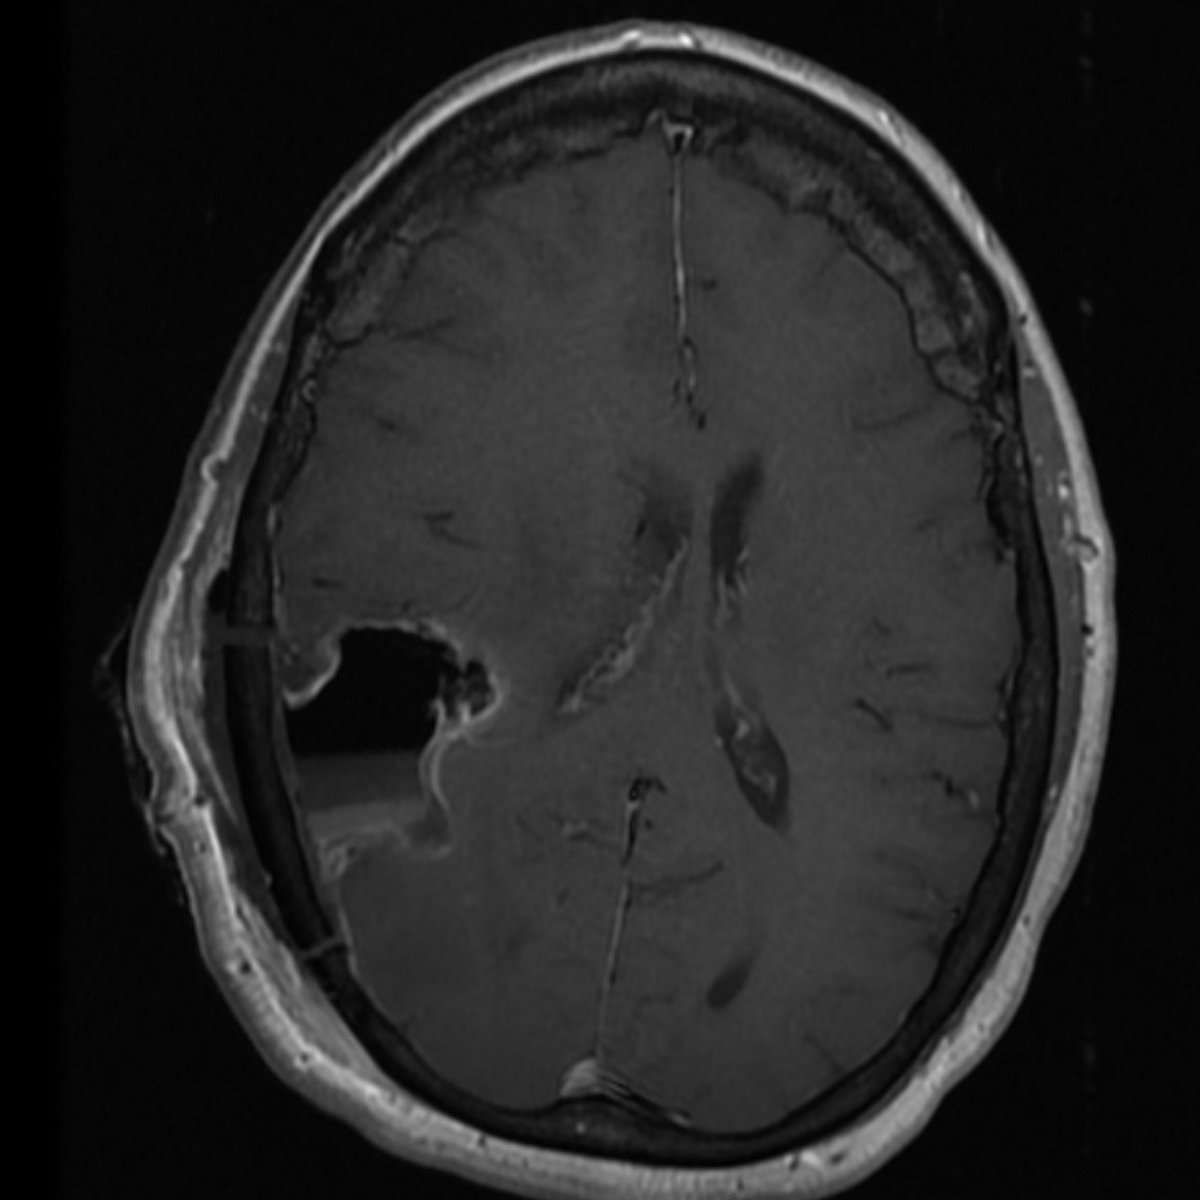

Great talk by @ShahidNimjee about VWF inhibiting aptamer for thrombolysis. This research has come along way and will improve stroke therapy in the future. It may be the beginning of the end of stroke mechanical thrombectomy. #SNIS2023 @OSUWexMed @NeurosurgeryOSU